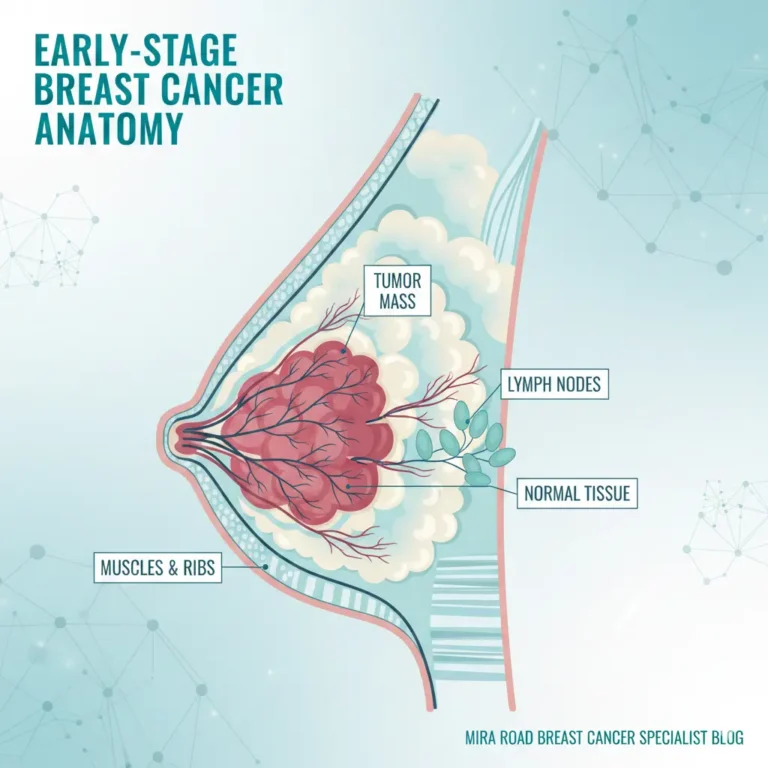

Essentials Advanced Breast cancer treatment in Mira Road. Breast cancer remains one of the most pressing health challenges worldwide, and surgical intervention…

Introduction Hearing the words breast cancer can feel overwhelming. If you’re here, you or someone close to you might be facing difficult decisions. One…

Hearing a breast cancer diagnosis can change your world in an instant. It’s normal to feel a flood of emotions, fear, confusion,…

If you or someone you love is facing breast cancer, the idea of surgery can feel overwhelming. In this guide, we’ll walk…

Breast Conservation Surgery In Mira Road If you’re reading this because either you or someone you love has recently been diagnosed with…